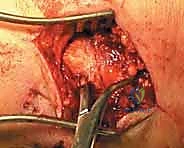

المرحلة الثانية: الشق الجراحي والوصول للعظام

يقوم الدكتور هطيف بعمل شقين جراحيين استراتيجيين:

1. شق على الجانب الخارجي (الوحشي): للوصول إلى عظمة الشظية المكسورة.

2. شق على الجانب الداخلي (الإنسي): للوصول إلى عظمة الظنبوب.

يتميز الأستاذ الدكتور بمهارته الفائقة في التعامل مع الأنسجة الرخوة، مما يقلل من تلف الأنسجة ويسرع من التئام الجروح.